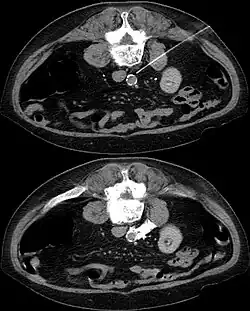

Sympathectomy under CT guidance. The patient lies on his stomach. In the first picture the injection needle is visible with its tip behind the aorta. The second image shows the distribution contrast with lysis bolus.

In CT guided lumbar sympathicolysis, the site of neurolytic solution injection is chosen at the level of L2-L3 vertebra level. The needle should avoid the vertebral transverse process, ureter, pelvicalyceal system, and other major blood vessels. The target injection site would be anteromedial to the psoas muscle and dorsolateral to the abdominal aorta, where the sympathetic trunk would most likely be located.[1]

After the skin of the puncture site is cleaned, 2% lignocaine is injected into the to numb the skin and also the needle trajectory. Then a 22G China needle is inserted into the target site, which is bounded by the vertebral body, aorta, inferior vena cava, and psoas muscle. This region houses the lumbar sympathetic ganglion. Then, iodinated contrast medium (iohexol) and lignociane is injected into the target site to check the position of the needle tip. Once the needle tip position is confirmed, a mixture of neurolytic solution (99.9% alcohol) and iodinated contrast medium (at a ratio of 10:1) is injected into the target site.[1]